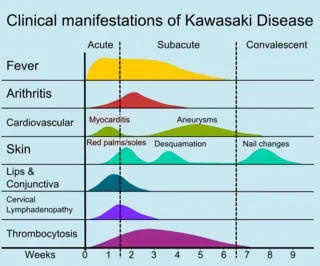

The course of the disease can be divided into three clinical phases.[47]

- The acute febrile phase, which usually lasts for one to two weeks, is characterized by fever, conjunctival injection, erythema of the oral mucosa, erythema and swelling of the hands and feet, rash, cervical adenopathy, aseptic meningitis, diarrhea, and hepatic dysfunction.[31] Myocarditis is common during this time, and a pericardial effusion may be present.[15] Coronary arteritis may be present, but aneurysms are generally not yet visible by echocardiography.

- The subacute phase begins when fever, rash, and lymphadenopathy resolve at about one to two weeks after the onset of fever, but irritability, anorexia, and conjunctival injection persist. Desquamation of the fingers and toes and thrombocytosis are seen during this stage, which generally lasts until about four weeks after the onset of fever. Coronary artery aneurysms usually develop during this time, and the risk for sudden death is highest.[15][48]

- The convalescent stage begins when all clinical signs of illness have disappeared, and continues until the sedimentation rate returns to normal, usually at six to eight weeks after the onset of illness.[31]